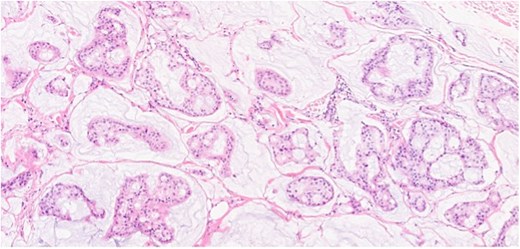

Herein, we present a 75-year-old man who, having been referred to our service with an inguinal hernia, raised concern about a palpable mass present in his right axilla. The main differential on initial examination was that of a simple epidermoid cyst, and consent was obtained for its removal during his elective hernia repair. Subsequent histology however, revealed a well differentiated MAC. There was extensive involvement of the deep and superficial reticular dermis (Figs 1and 2). Lymphovascular invasion was present. Sweat glands were focally involved by the carcinoma. The differential diagnosis included PCMC and metastasis from other primary sites of MAC such as breast, lung and gastrointestinal. Immunohistochemical profiling was performed on the specimen. CK 7, HER2 (4B5, 3+), GATA3 (strong, diffuse), and P16 (focal, weak) were positive (Figs 3–6). SOX10, CK 20, CDX2, TTF-1, p40, ER, and PR were negative which supported the diagnosis of MAC with either breast or PCMC origin based particularly on GATA3 expression.

(a, b) Section of skin showing dermal lesion composed of nests of tumor cells floating in pools of extracellular mucin.

Section showing tumor cells with low to intermediate nuclear grade floating in pools of extracellular mucin separated by fibrous septa.